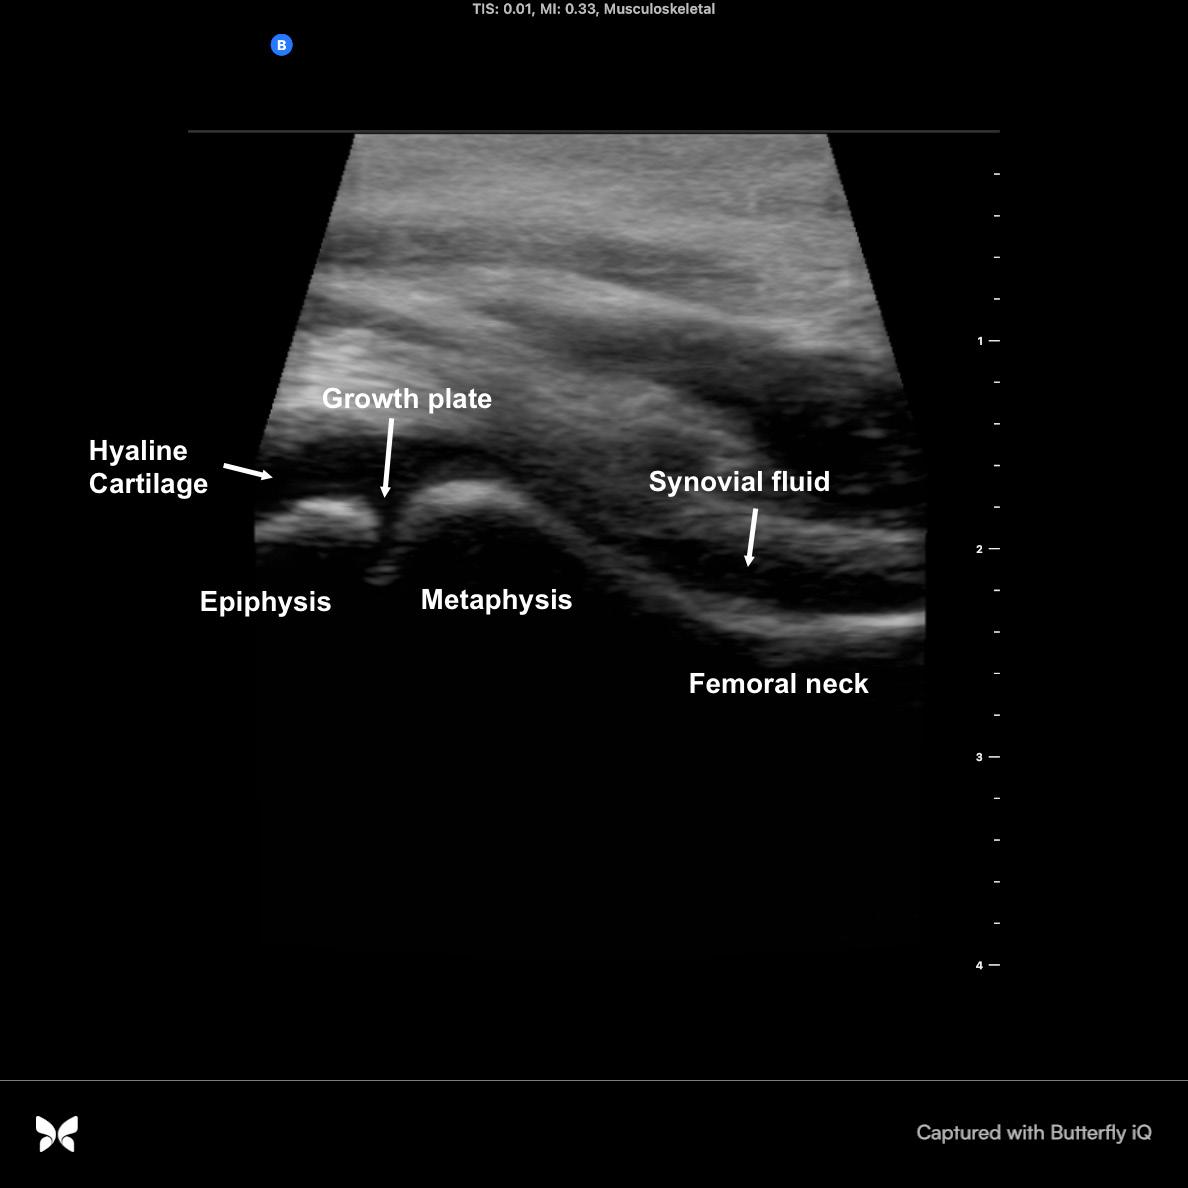

Not Just Small Adults: Tailoring Point-of-Care Ultrasound Skills for Pediatric Patients

Point-of-Care Ultrasound in Acute Monocular Vision Loss